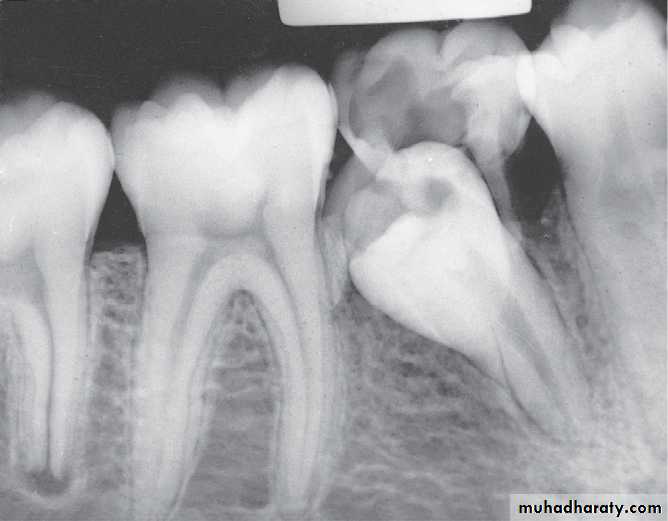

Infected mandibular second primary molar

has caused hypoplasia of the second premolar and delayed eruption of the tooth.Pre-eruptive “caries” on the crown of an

unerupted first premolar (arrow).